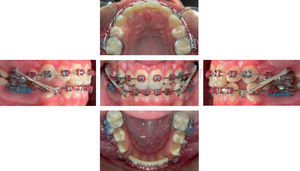

After two months open coil springs were used between the lateral incisors and the upper premolars to maintain space for the retained canines and lower canine retraction was begun with elastic chains (EC) over 0.018” stainless steel (SS) archwires (Figure 3).

Eight months later, the lingual arch was withdrawn and a lower 0.019 x 0.025” nitinol archwire was used to include the upper canines in the arch (Figure 4).

Once the leveling was complete, we began closing the lower spaces, 0.019 x 0.025” stainless steel archwires with crimpable hooks were placed, the posterior teeth were blocked out (to disarticulate and favor movement) and active lace backs that are changed monthly during control appointments (Figure 5).

Retraction of the lower anterior segment was supplemented with the use of class III vector 3/16” 31/2 ounce-intermaxillary elastics. At that moment the posterior block out were removed and placed anteriorly thus maintaining a distal position of the mandible; for two months this was the chosen mechanics and in the next appointment a dental class II relationship was observed associated with the use of intermaxillary elastics. A tomography of the condyle with open and closed mouth, a lateral headfilm and a panoramic radiograph were suggested to assess the condylar position (Figure 5).

Once the axial tomography and the pan were assessed, a proper position of the condyle was found and it was decided to lose the lower anchorage mechanics and the use of intermaxillary elastic with vector II Class of nocturnal use was prescribed thus restoring the lost canine class I relationship (Figure 6).